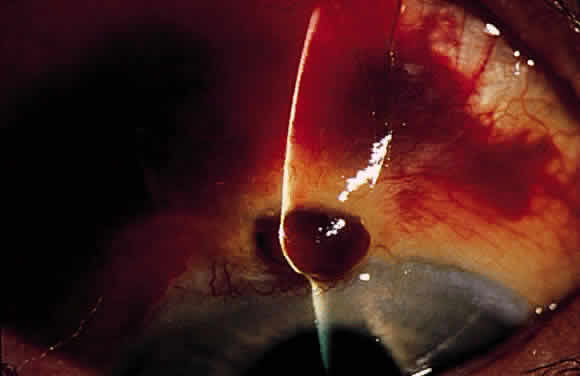

Aqueous misdirection usually occurs in the early postoperative period after filtration or cataract surgery. The anterior chamber is shallow, and the IOP is high (Fig. 6). However, with a functioning filtration bleb, the IOP may not be high. The peripheral iridectomy is patent, and a dilated examination and B-scan ultrasound confirm the absence of choroidal effusion of hemorrhage. If the adequacy of the surgical iridectomy is in doubt and pupillary block is possible, a laser iridotomy should be performed.

Three conditions should be considered in patients with postoperative flat anterior chamber and elevated or normal IOP: suprachoroidal hemorrhage (see earlier), aqueous misdirection, and pupillary block.

FLAT ANTERIOR CHAMBER AND ELEVATED OR NORMAL INTRAOCULAR PRESSURE